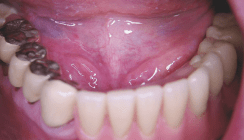

Der individuelle Aufbau, der im Gegensatz zu präfabrizierten Abutments ein zahnanaloges Durchtrittsprofil erlaubt, wurde nach minimalinvasiver Freilegung eingegliedert. Damit übernimmt er die Funktion eines „keramischen Gingivaformers“. In diesem Fall ist das Implantatprotokoll zugunsten eines zügigen Ablaufs verändert, denn so konnte ein weiterer Wechsel des Abutments vermieden werden. Grundsätzlich kann bei verkürztem Ablauf ein Beschleifen des Aufbaus notwendig werden. Nach einer provisorischen Tragedauer von 14 Tagen wurde der Gingivaverlauf am Abutment überprüft (Abb. 7 und 8). Es lag eine reizfreie Gingiva um die epigingivale Stufe vor, sodass die Zirkonoxidkrone definitiv eingegliedert werden konnte (Abb. 9–11).